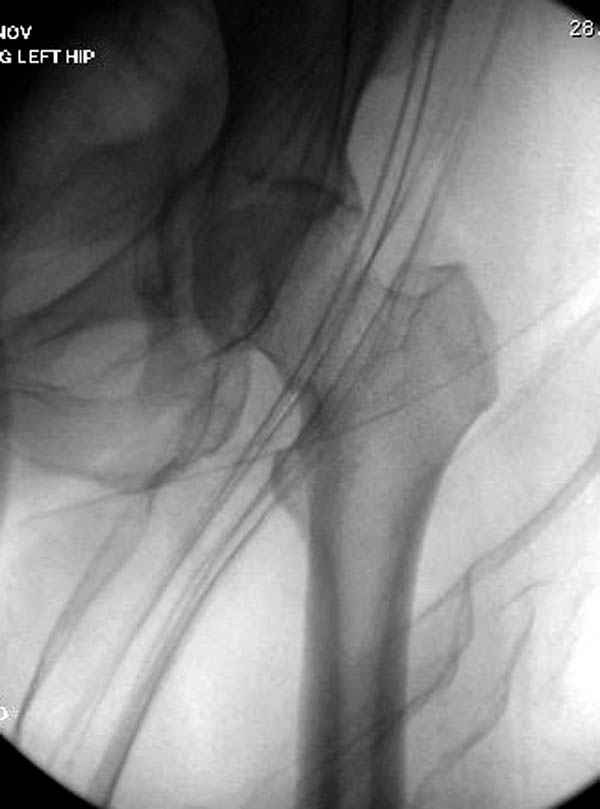

Отправлено Коваленко А.Н. 15 Январь 2008, 03:51

Уважаемые коллеги! С прошедшеми Вас праздниками. Теперь ближе к трудовым будням. Поступила 16 летняя девушка неделю назад. Механизм травмы падение с 5 этажа. Краткий диагноз:закрытый перелом левой ключицы, левого плеча, закрытый вертикально и ротационно нестабильный перелом костей таза:закрытый перелом левой подвздошной кости, переломы лонной кости справа, перелом обоих колонн вертлужной впадины слева;субкапитальный перелом шейки левой бедренной кости со смещением. По тактике лечения таза возникли следующие вопросы: 1. С чего начать - фиксации переломов вертлужной впадины или устранения деформаций таза? 2. Надо ли фиксировать шейку или фиксировать бедро в аппарате вместе с тазом, а после сращения таза планировать ТЭП ТБС? Если имеются еще какие подводные камни, будем рады выслушать.Спасибо.

Долгое ожидание повышает риск АВН головки,

рекомендуется ургентная фиксация шейки в первые сутки, а в дальнейшем таз.

В данный момент скелетное вытяжение поучается через перелом шейки, а фиксированный перелом шейки будет участвовать в процессе вытяжения через каннюлированные шурупы.

Перелом шейки смогли зафиксировать через пару дней, ацетабулум до сих пор не оперирован, на вытяжении.

Из-за упущенного времени (три недели с момента

поступления) ацетабулум ведем консервативно.

На снимке ацетабулума редко встречающийся очень низкий перелом, наверное, трудно было репозицию через один доступ? Перелом как бы замкнулся в квадрилатеральной поврехности.